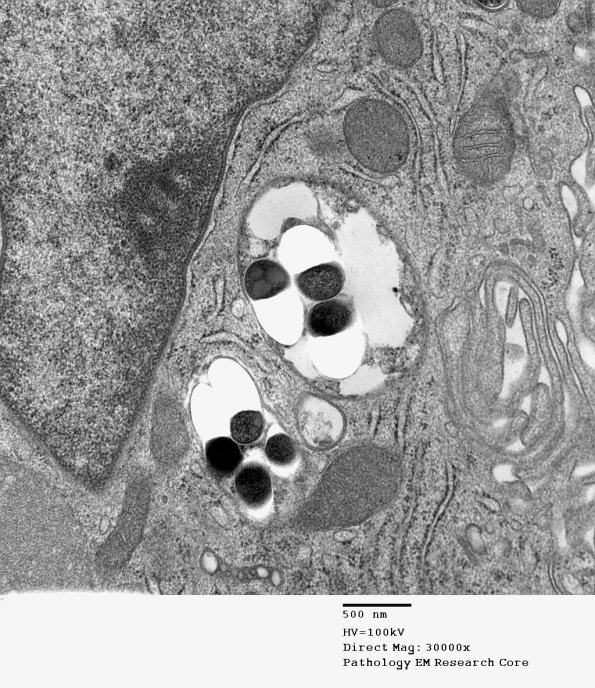

Higher magnification of image #1D10A. (electron micrograph)